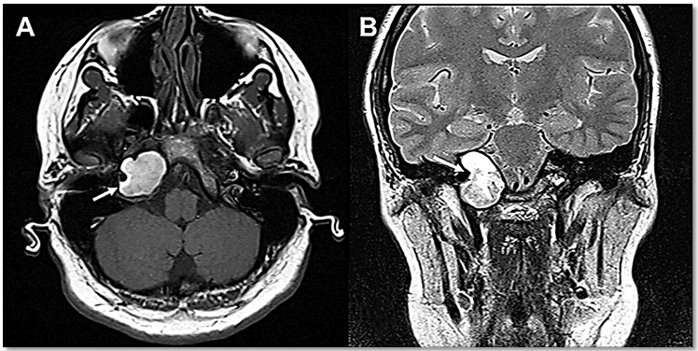

Homem, 50 anos, com quadro de perda auditiva neurossensorial à direita de grau

leve, é submetido a estudo de ressonância magnética sem contraste, onde foram observadas as

seguintes imagens: